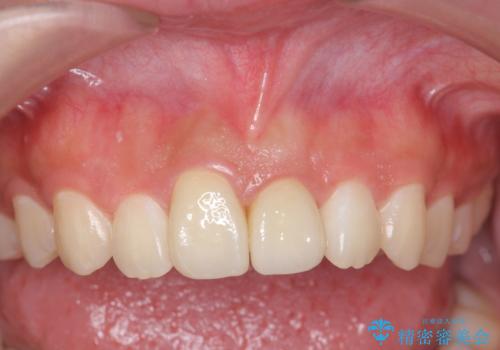

治療結果には大変満足されていました。

- 31万円(ジルコニアクラウン(スタンダード)10万円x2、仮歯 1万円x2 ファイバーコア 2万円x2 ジンジペクトミー 5万円)費用は治療当時の料金となります

笑っても大きく歯ぐきが見える方ではなかったので、歯ぐきのラインが目立つことはなかったです。

矯正治療もご自身の歯を生かしていけますが、後戻りの問題や、前歯のみを動かすことが不可能なため、セラミック治療と同じくメリット、デメリットがあります。